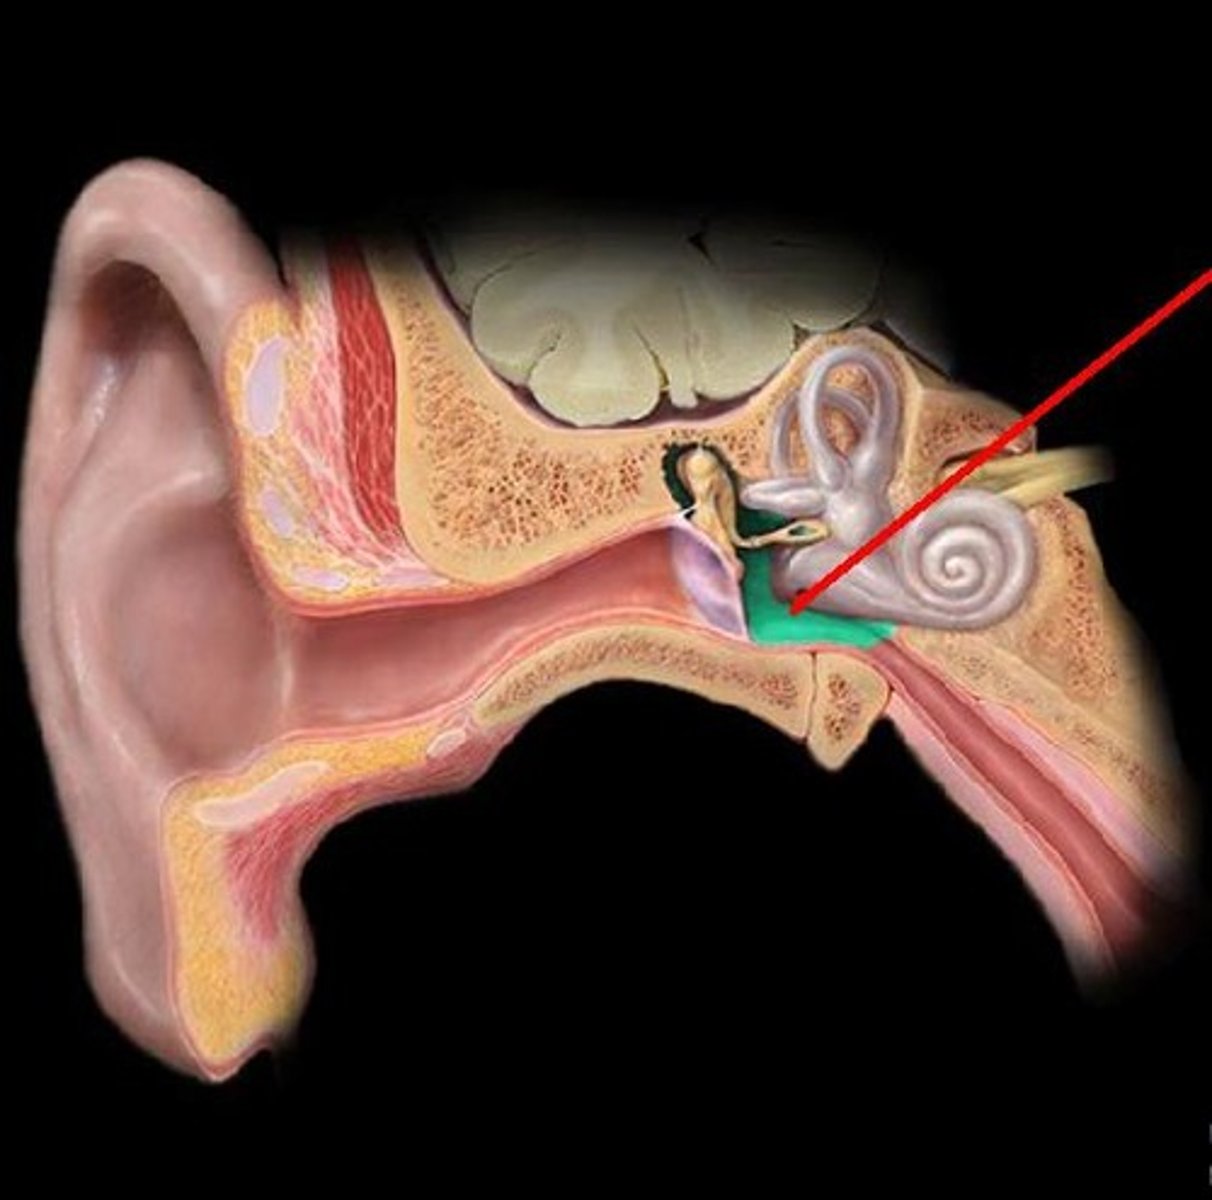

auditory ossicles

tympanic membrane

tympanic cavity

coclea

semicircular canals